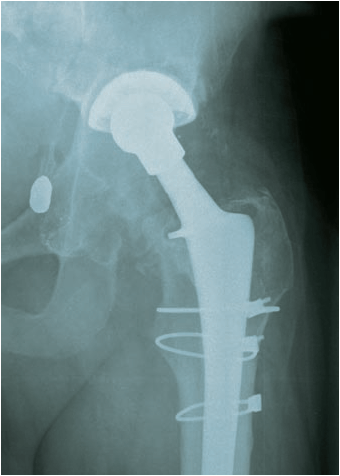

- Then most likely press-fit the revision femoral stem which will be a little longer than the stem used first time round. And it will be flanged – a Zimmer implant.

Finished job with the wires should look a little like this:

Then the next step will be to dig out the acetabular cup – which is press fitted in – despite the original surgeon’s notes saying it was cemented!!!

Most likely there will be a need for a bone graft or some form of packing & screws for the new cup.

Then in goes the ceramic insert and femoral head – presto; a new man!

Had some new X-rays done today – two months since the last ones – seems to me that there is more osteolysis and bone loss – possibly some fragments but I am not a medical doc and I haven’t discussed these with the surgeon yet. Will do on the day of the surgery.

What is interesting is 3 radio-opaque spots showing up in the pelvic area – not sure what those are.

Quality of the photo’s below – OK for an iPhone 4 shot of the X-Rays held up by my son against a white background!